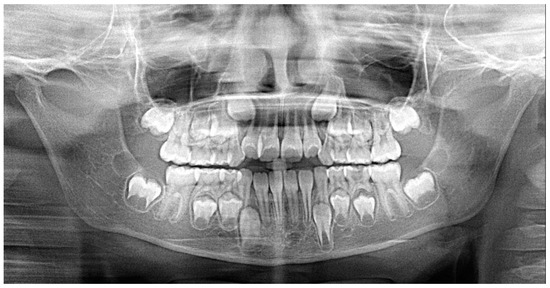

2.1. Patient’s Clinical Characteristics